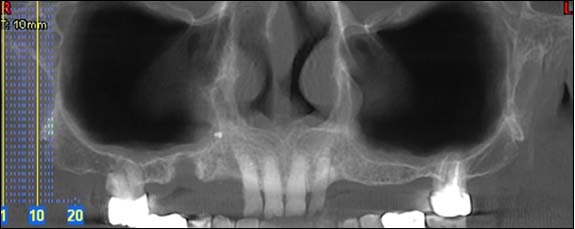

EXAMENS TOMOGRAPHIES VOLUMIQUES TYPE SCANNER OU CÔNE BEAM :

Dernière technologie à notre disposition, cette technique permet de voir en 3 dimensions des images de votre bouche et de mettre en évidence des pathologies ou des anomalies que les autres techniques ne permettent pas d’objectiver.

Reconstruction coronale